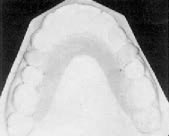

Outline the body of the appliance on a stone cast. Adapt the clasps against the cervical margins and beneath the heights of contour of the tooth surfaces distal to the extraction sites (Fig. 3). Do not extend the clasps facially to the extent that they bind against the archwire when the patient removes the appliance for cleaning.

Adapt the acrylic firmly against the lingual surfaces of the molars. Do not include the horizontal part of the hard palate; this would not contribute to the anchorage unit, but would make the appliance more bulky and decrease tongue space. An anterior or posterior bite plane can be incorporated if necessary.

Do not place acrylic in the path of the teeth to be retracted or in the cervical area of the anterior teeth. This avoids bunching of the tissue between the incisors and the appliance during retraction. Anchorage will not be affected, because the vertical component of the anterior palate, not the incisors, is primarily responsible for buttressing the posterior teeth.

Fig. 3 Palatal shelf anchorage appliance outlined on cast, with clasps adapted against cervical margins and beneath heights of contour of second premolars. Only vertical slopes of palate are covered with acrylic; appliance does not butt against incisors.